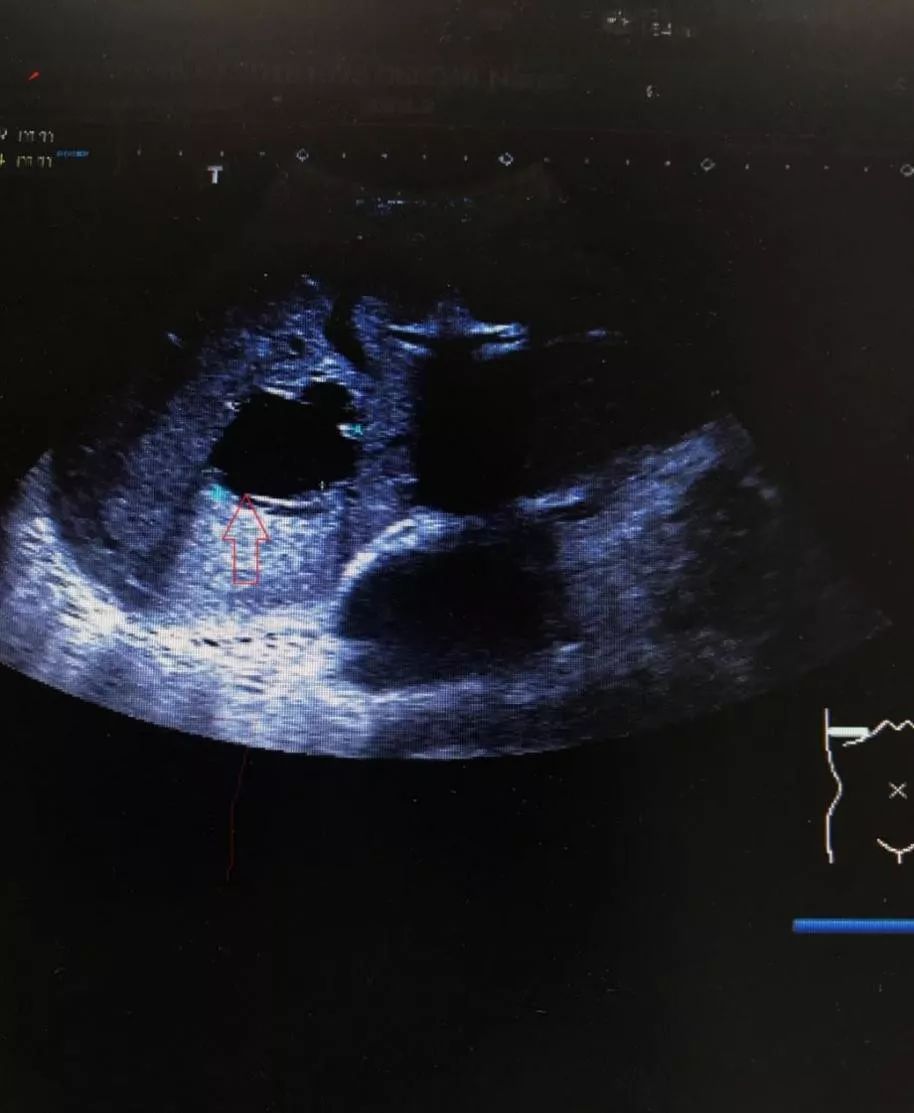

图一

Smaller cysts of just a few millimeters